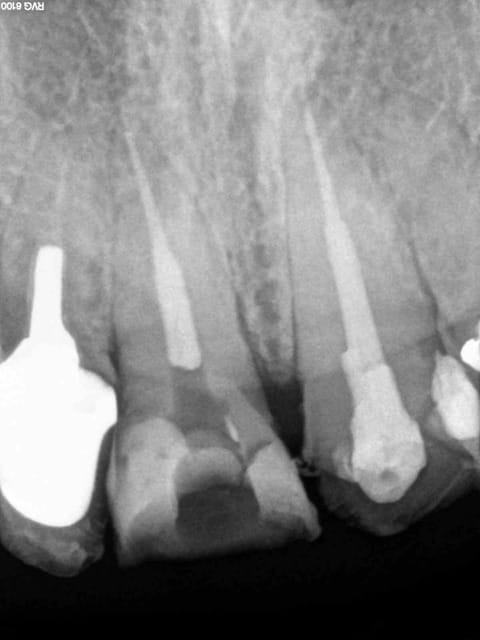

11 21 de la balle crjq1n - Eugenol

Pose 2 ic coiffe 10 mn mxgarl - Eugenol

11 21 endo turbo so1akt - Eugenol